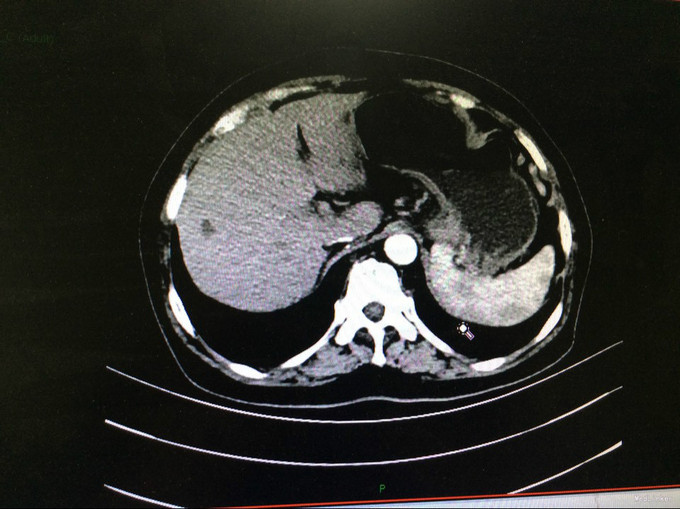

查体:生命体征平稳。神智清,查体合作,面容正常,淋巴结未触及肿大。双肺听诊呈清音,为闻及干湿罗音及哮鸣音;心率78次/分,律齐,无异常心音及心脏杂音;腹平软,肝脾肋下未及,未触及肿块,无压痛及反跳痛,肠鸣音正常。双下肢无水肿,生理反射存在,病理反射未引出。专科查体:无明显异常。辅助检查:湖北省中医院CT示:胰腺占位。CT检查示:1.结合原CT、MR检查,胰腺体尾部及周围异常改变,考虑胰腺炎伴坏死囊性变可能性大,与2015-11-20CT相比较,囊性病变略缩小;腹膜后淋巴结增多增大,大致同前;2. 所及肝脏多发囊肿;肝右叶后段其中一个病变边缘可疑强化,大小与前次相仿;3. 左侧肾上腺饱满。 MRI检查示: 胰腺体尾部及周围异常改变,考虑胰腺炎伴坏死囊性变可能性大,合并肿瘤性病变待排,病变累及腹膜伴腹膜后淋巴结增多增大,腹腔少许积液,请结合检查结果考虑;2. 所及肝脏多发囊肿;肝右叶后段其中一个病变边缘可疑强化,需鉴别于血管瘤与转移性病变,建议随访复查;3. 左侧肾上腺饱满;4. 所及右侧胸廓外小结节(层面16-7),直径约4mm,不除外右乳的病变:5. 所及腰椎骨性纵裂畸形。病理检查:(胰体尾部肿块穿刺组织)高分化腺癌,考虑为IPMN相关性浸润性癌。